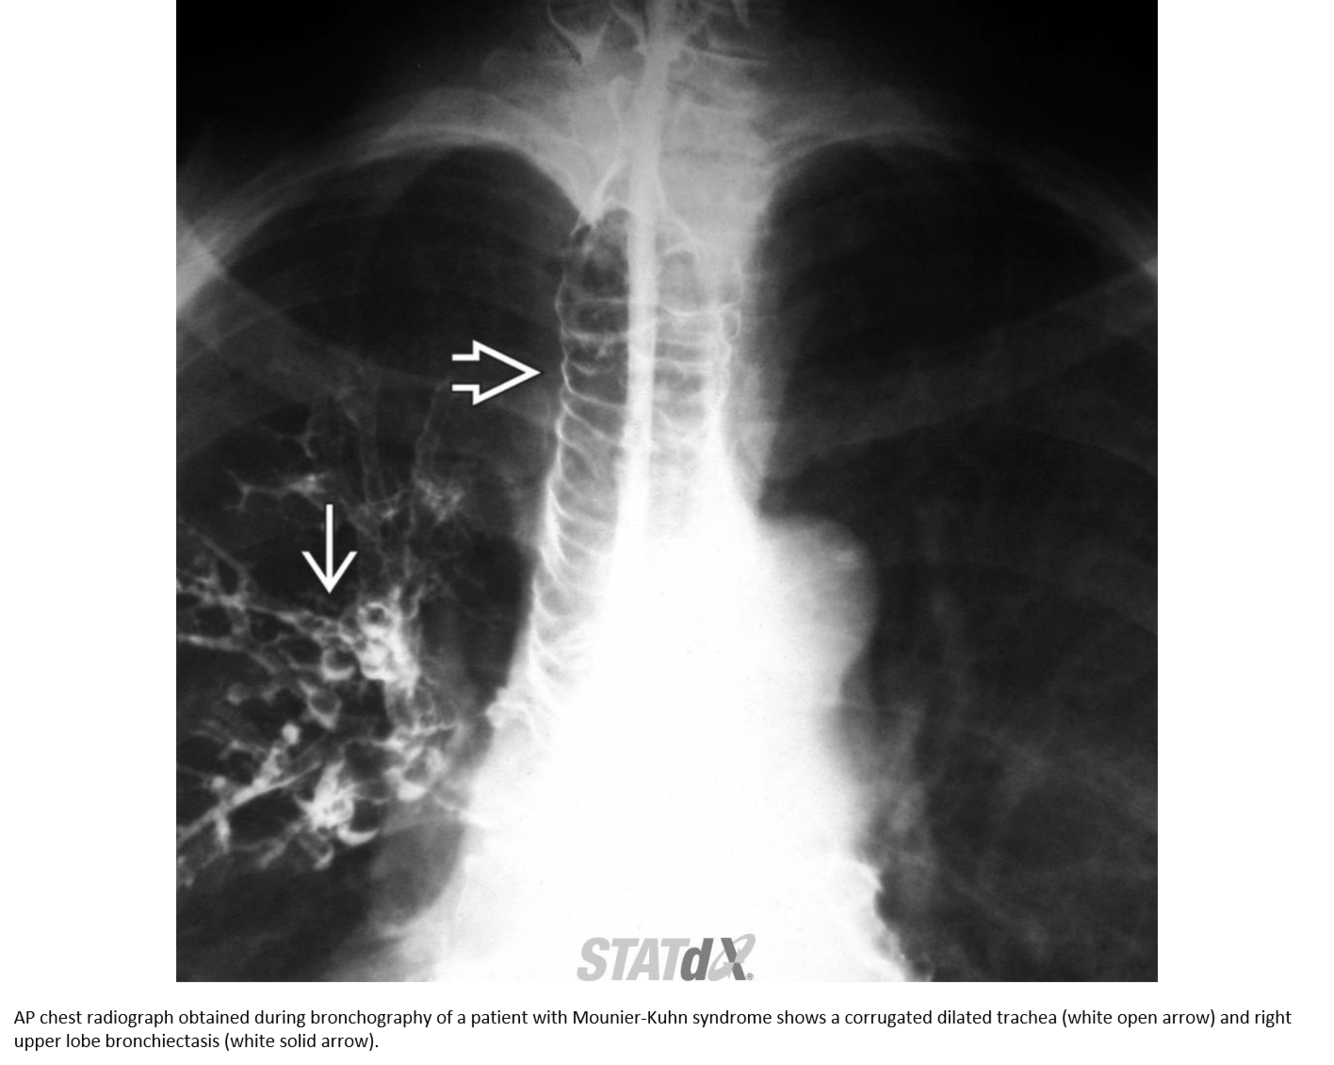

Tracheobronchomegaly (Mounier-Kuhn syndrome)

Dilatation of trachea & central bronchi that impairs ability to clear mucus

Atrophy or absence of elastic fibers & thinning of smooth muscle layer in trachea & main bronchi

Tracheobronchomegaly; Mounier-Kuhn syndrome

Coronal CECT of a patient with tracheobronchomegaly shows marked dilatation of the trachea (open arrow) and mainstem bronchi . The large airways have a corrugated appearance. Right lower lobe pneumonia (straight arrow) and paraseptal emphysema are also present.